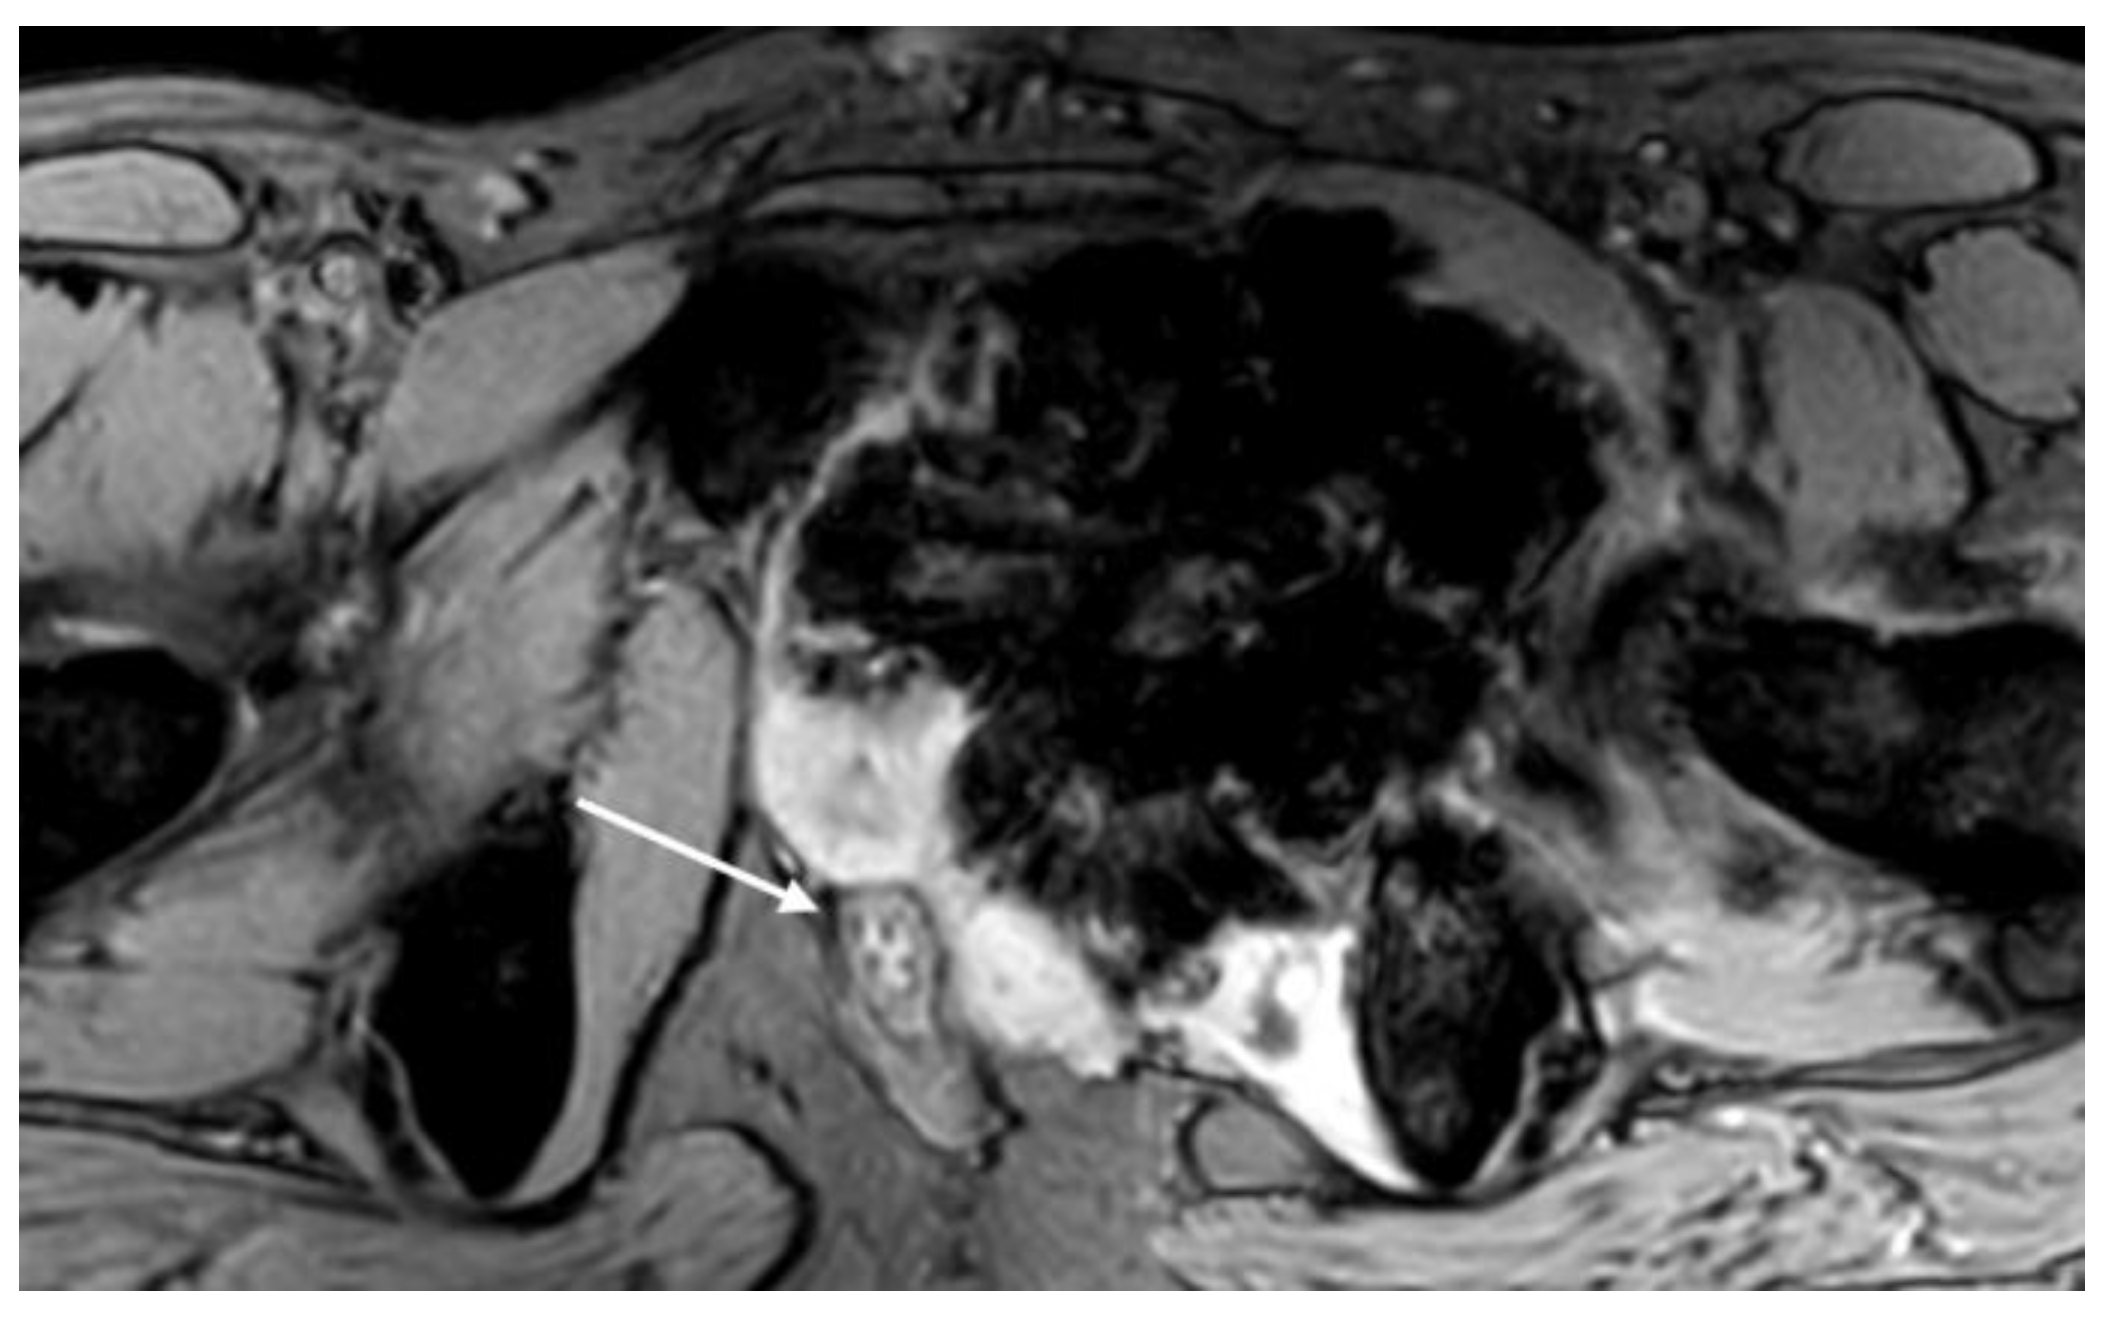

3.1.2. Secondary Osteosarcoma

3.2.3. High-Grade Surface Osteosarcoma